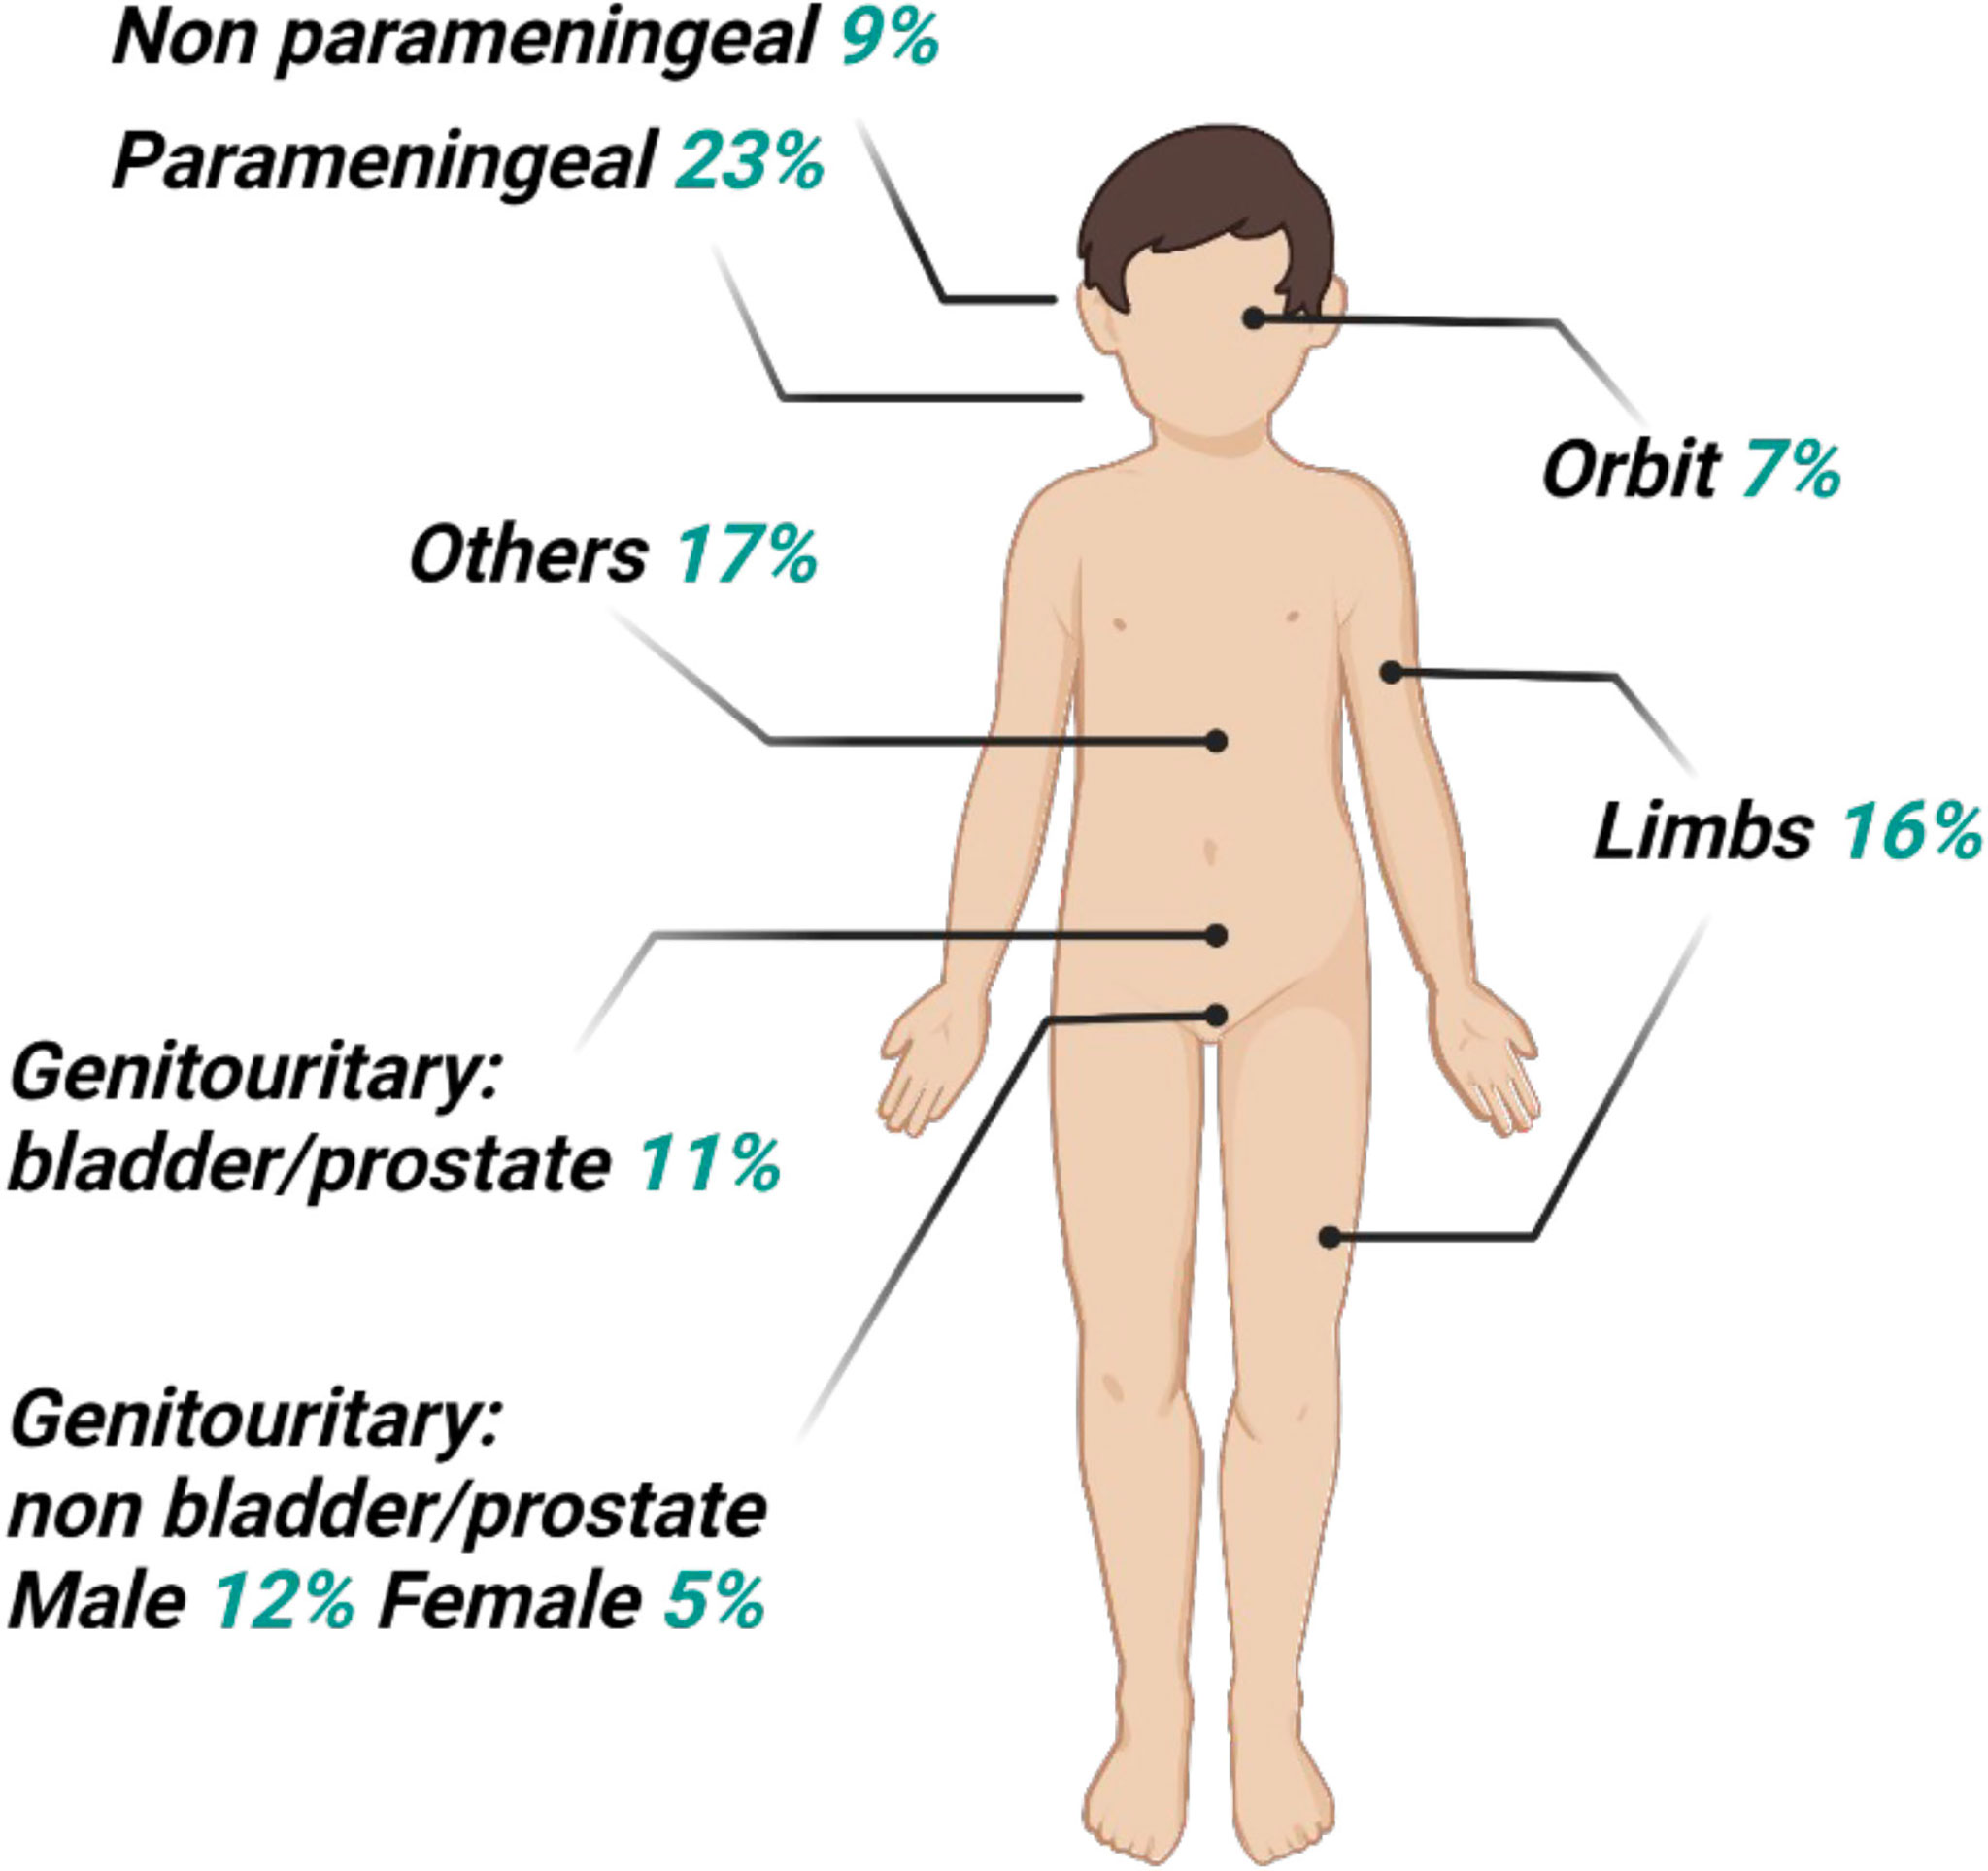

Diagnostics | Free Full-Text | Usefulness Of 18f-FDG PET-CT In Staging

www.mdpi.com

www.mdpi.com